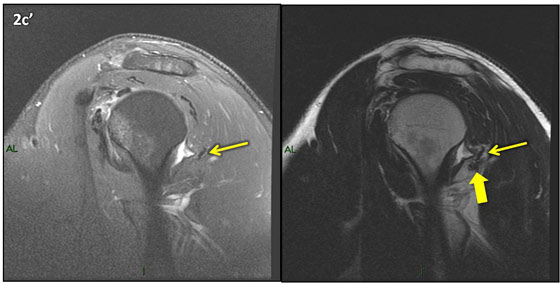

Figura 2 (a-j)': Imagens consecutivas de RM no plano sagital nas ponderaçõesT2 com supressão de gordura (DP SG) à esquerda e T2 à direita. Clique na seta para passar as imagens.

Figuras 2b a 2j’: Acompanhando o tendão do redondo menor (seta amarela fina) é possível notar lipossubstituição ao redor da junção miotendínea (setas amarelas grossas) e a atrofia principalmente da porção mais lateral (seta salmão). A porção mais medial (seta branca) tem volume preservado.

Repare que estas alterações também não são evidentes nas imagens com supressão de gordura no plano sagital.

Essa diferença entre os estudos pode ser em parte explicada pelo reconhecimento ou não de que o músculo redondo menor apresenta duas porções anatomicamente distintas e independentes, uma mais superior, que se insere no tubérculo maior, e outra mais inferior, que se insere no colo cirúrgico do úmero, e que a atrofia pode ocorrer em apenas uma delas e passar despercebida.

Chafik et al. também relataram a presença de um pequeno nervo motor acessório em número variável que se insere na porção lateral do músculo redondo menor. O nervo acessório, ao contrário do principal, tem um curso reto e extra-fascial, sendo menos vulnerável aos efeitos compressivos. De fato, nos casos da atrofia parcial do redondo menor, é mais frequente a atrofia da porção mediodorsal com preservação da porção lateroventral, o que poderia ser explicada pela presença do ramo acessório mais lateral do nervo axilar, embora atrofia isolada do componente lateroventral tenha sido reportada em cerca de 17% dos casos de atrofia de apenas uma porção, o que pode ter sido causada por lesão do nervo acessório. No caso do paciente deste mês, a atrofia é mais evidente nesta porção mais lateral e ventral do redondo menor.

É importante que o protocolo de ressonância magnética do ombro tenha sequências ponderadas em T1, T2 ou densidade protônica (DP) sem supressão de gordura em pelo menos dois planos, idealmente nos planos coronal e sagital, para a detecção de lipossubstituição que pode passar despercebida nas imagens com supressão de gordura.